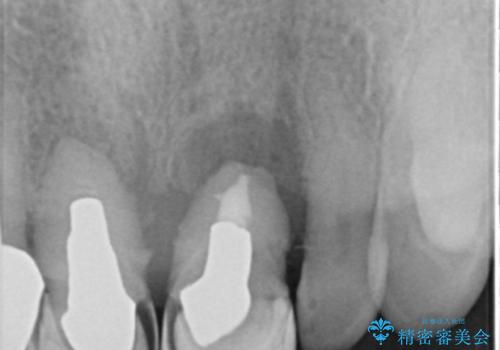

- 上下の前歯が抜けそうだとのことで来院されました。

精査したところ、動揺の著しい上下の前歯は重度の歯周病により保存不可能と判断しました。

上の前歯の再根管治療もおすすめしましたが、必要性を感じないとのことで土台のやりかえだけをご希望されました。